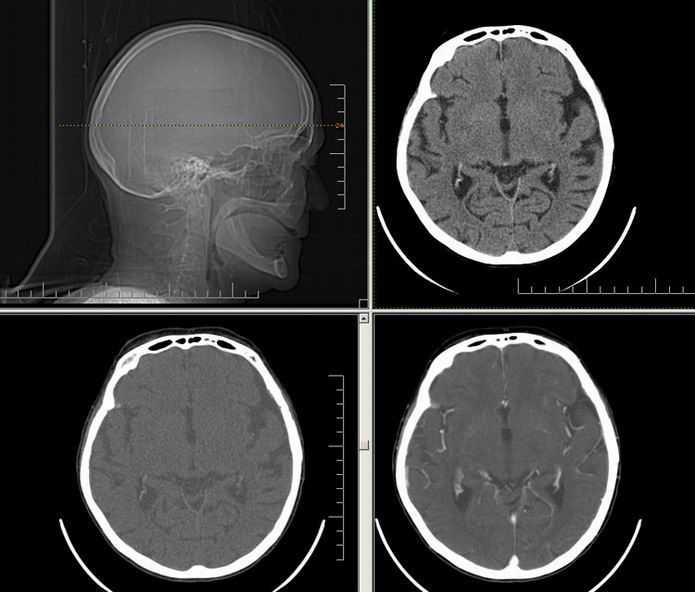

Est ce que qqun a des coupes axiales de crâne pour m'aider à réviser mon anatomie. Merci

Pour compléter tes révisions, Poupette vient de nous faire parvenir ces planches bien utiles: Planches de coupes axiales cérébrales, dans la rubrique COURS / ANATOMIE